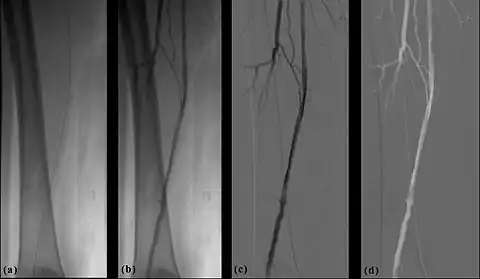

Digital Subtraction Angiography (DSA), as the name implies, involves an image subtraction technique - see Figure 7.1. As will be seen below, the technique involves more than simply applying a subtraction process in the digital image processor. In addition, it will be seen that the type of technology utilised, while based on the design of fluoroscopy systems, needs to incorporate a number of modifications unique to DSA. Before addressing the technology however, some basic physics needs to be introduced which will aid in putting the subsequent technology discussion into context.

- The process of subtraction angiography, as illustrated simplistically in Figure 7.2, involves the subtraction of a post-opacification image (commonly called the Live image) from a pre-opacification image of the same region (commonly called the Mask image). When it is assumed that monoenergetic X-rays irradiate the patient and that no scattered radiation is generated, the radiation intensity, I2, for an appropriate point of the live image is related to the intensity, I1, for the same point of the mask image, by:

- The temporal-averaging feature of digital noise reduction can also be used for image presentation purposes so that the time course of the movement of contrast medium during a study can be displayed using just one image - see an example in Figure 7.4 from the peripheral study shown above - instead of a sequence of numerous images. Such an image is sometimes referred to as a Vascular Trace.

- One method of temporal filtration, referred to as Integrated Mask-Mode DSA involves adding (also called integrating) a number of images, acquired prior to the arrival of the contrast medium, to form an integrated mask image and adding a number of peak-opacification images to form an integrated live image. This is the process that was used to generate the vascular trace image in Figure 7.4. Thus, when four images are used to generate each integrated mask and live images, eight of the 25 images are now used in the subtraction process and, as a result, only 68% of the dose is wasted, and a subtraction image with lower noise results.